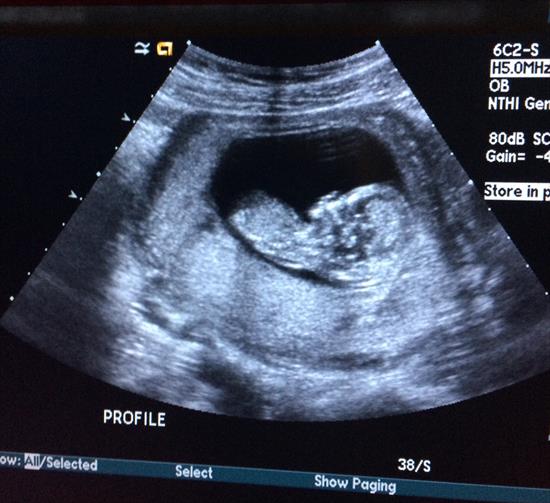

I'll add all of the photos I have. A leg isn't showing in the potty shot so I drew it in for a better idea. i just can't believe that this could be a boy - it looks nothing like any others I've seen. What are your thoughts? Would you announce going off of these images?

Attachment 28149Attachment 28153Attachment 28150Attachment 28151